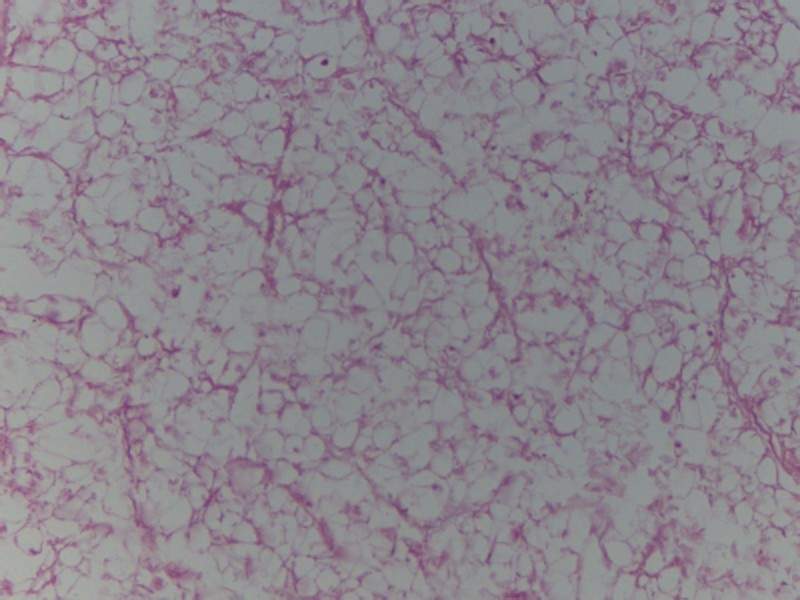

[求助] HE染色能观察移植细胞状态吗

各位师兄师姐好,我之前做了一些犬的坐骨神经支架,然后用注射的方式沿纵轴移植了一些骨髓间充质干细胞进去,7天后固定做了HE染色,我想请问一下就根据HE染色能不能判断移植的细胞是死是活!

我感觉看着细胞形态好像还算完整,但是移植后装有神经支架的培养基里的细胞贴壁后总是有空白区,没有污染的杂质之类的东西出现,支架脱细胞很干净,使用的是TritonX-100和脱氧胆酸钠,请问如果移植细胞没有存活,那可能的原因是什么,希望各位高手帮忙解答,小妹非常感激

脱细胞神经 横 40.1.JPG

移植细胞。纵。40.1.JPG